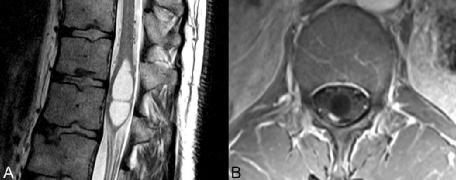

▲图 51.5

与之前讨论的肿瘤一样,血管母细胞瘤也倾向于髓内,尽管它们更常见于颈部和胸部,在整个脊髓中也相当罕见。多发性脊髓血管母细胞瘤是冯·希佩尔-林道(点击)的病理特征。外观可能为实性或囊性,后者在大型髓内病变中更常见,如图51.5 A、B所示。囊性成分的信号因蛋白质含量而异。在所示的患者病例中,造影前序列上没有可轻易识别的实性病灶。虽然大囊性转移瘤可能具有类似的外观,但在FSE T2WI上来自扩张脑膜静脉的流动空洞的存在几乎是血管母细胞瘤的病理特征。在(B)轴位增强T1WI上,囊性部分的后外侧可见明显强化的病灶,该区域与囊性部分相比很小。

尽管未在此处见到,但与脊髓血管母细胞瘤相关的水肿可能使其与转移性病变的区分更为复杂。